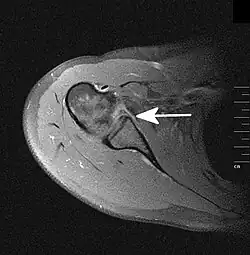

Grundlage ist die Anamnese (Unfallmechanismus) und körperliche Untersuchung (Funktionseinschränkung). Dabei muss insbesondere die Schädigung von Blutgefäßen und Nerven beachtet und dokumentiert werden. Durch Röntgenbilder in verschiedenen Ebenen wird die Diagnose gesichert und eine Fraktur ausgeschlossen. Zum Ausschluss einer Bankart-Läsion (s. u.) kann eine MRT-Aufnahme angefertigt werden.

Als Hill-Sachs-Delle bezeichnet man eine Knochenimpression am Humeruskopf. Sie kann durch eine Unterfütterung mit Spongiosa oder eine Drehosteotomie (nach Weber, nur noch selten angewandt) behandelt werden. Unter einer Bankart-Läsion versteht man den Abriss des knorpeligen Labrum glenoidale inferius von der Gelenkpfanne. Daraus kann eine vordere Schulterinstabilität resultieren. Die operative Therapie besteht in einer arthroskopischen Refixierung (Bankart-repair) oder einer Rekonstruktion mittels eines Knochenspans, z. B. in der Technik nach Latarjet. Beide Läsionen sind Risikofaktoren für ein rezidivierendes Auftreten weiterer Luxationen.